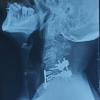

Post-operative X-ray – (Fig. 5)

The surgical team performed a posterior decompression and stabilization from C3 to C5, a preferred approach for addressing multi-level compression injuries involving cervical spinal fractures. A laminectomy at C4 and C5 was conducted to relieve spinal cord compression, and pedicle screws and rods were placed from C3 to C5 for stabilization. This approach provided the necessary support to reduce the risk of further spinal cord injury and promote neurological recovery. Post-operatively, the patient was managed with neuroprotective strategies, including corticosteroids, to control inflammation and spinal immobilization to support healing (Liu and Li, 2020) [4].

Following surgery, the patient showed notable neurological improvement. Upper limb motor function improved to 3/5, while lower limb strength increased to 1/5. Sensory function returned to normal (2/2) in both the upper and lower limbs. The patient was then enrolled in an intensive rehabilitation program, focusing on physical therapy to further enhance motor function, maintain joint mobility, and prevent complications such as muscle atrophy and pressure sores (Tator et al., 2019) [5].

At the latest follow-up, the patient exhibited significant neurological improvement. Motor power in the upper limbs improved to 3/5, with complete sensory recovery graded at 5/5. In the lower limbs, motor strength also progressed to 3/5, and sensation was fully restored to 5/5. Functionally, the patient was able to perform most daily activities independently, with ongoing rehabilitation aimed at further strengthening lower limb function and enhancing mobility. The overall outcome indicated substantial recovery following early decompression and stabilization.